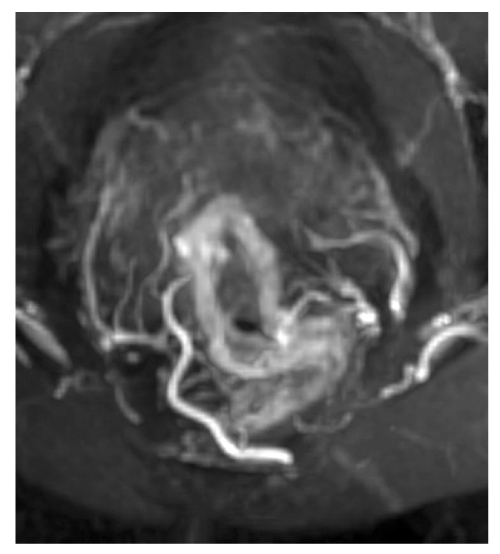

In 34% of cases, two branches of the upper rectal artery were identified, leading to trifurcation. The posterior branches branched off in the form of arcs to the posterior wall of the intestine at 5 and 7 o’clock of the conventional dial (variant 2). Figure 6 displays the first and second variants. In two observations, a vascular arcade in the form of an arc was found, which fed almost the entire circumference of the intestine, according to the blood supply type of the small intestine (variant 3) (Fig. 7). In six cases, variant 4 (Fig. 8) showed the scattered type, with six separate branches from the superior rectal artery to the intestinal wall, either simultaneously or consecutively. In 4% of cases, variant 7 had four branches of the upper rectal artery, two of which split and two went separately.

Fig. 7. Arterial arcade of the rectal wall: MIP reconstruction of magnetic resonance tomography.